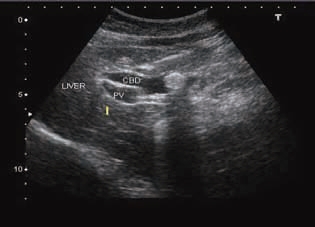

(1)肝外胆管扩张,与门静脉主干形成双筒猎枪征(图5-14)。扩张的胆管壁可增厚,回声增强,内壁欠光滑。结石部位在胆囊管以上者胆囊不增大;结石部位在胆囊管内或以下胆管者胆囊增大;结石在胆总管则可以引起整个胆管系统的扩张。

图5-14 胆总管结石(强光团处)并扩张呈双筒猎枪征

CBD:胆总管;PV:门静脉;LIVER:肝。